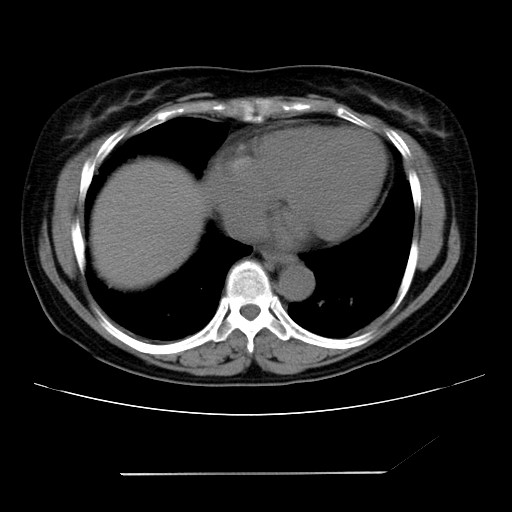

女性,62岁,长期咳嗽,既往从事工作有粉尘接触,有高血压病史,110/150mmhg,近日咳嗽加重,脸面浮肿,请大家帮看下,

1、尘肺;2、慢性支气管炎合并肺部感染;3、心影增大(左房、左室大),考虑高血压性心脏病。

慢支并肺部炎症;右肺结核球?主肺动脉、右肺动脉影不宽,右心室不大,不支持肺心病;无心包积液。

右肺无结核球,是肝上缘